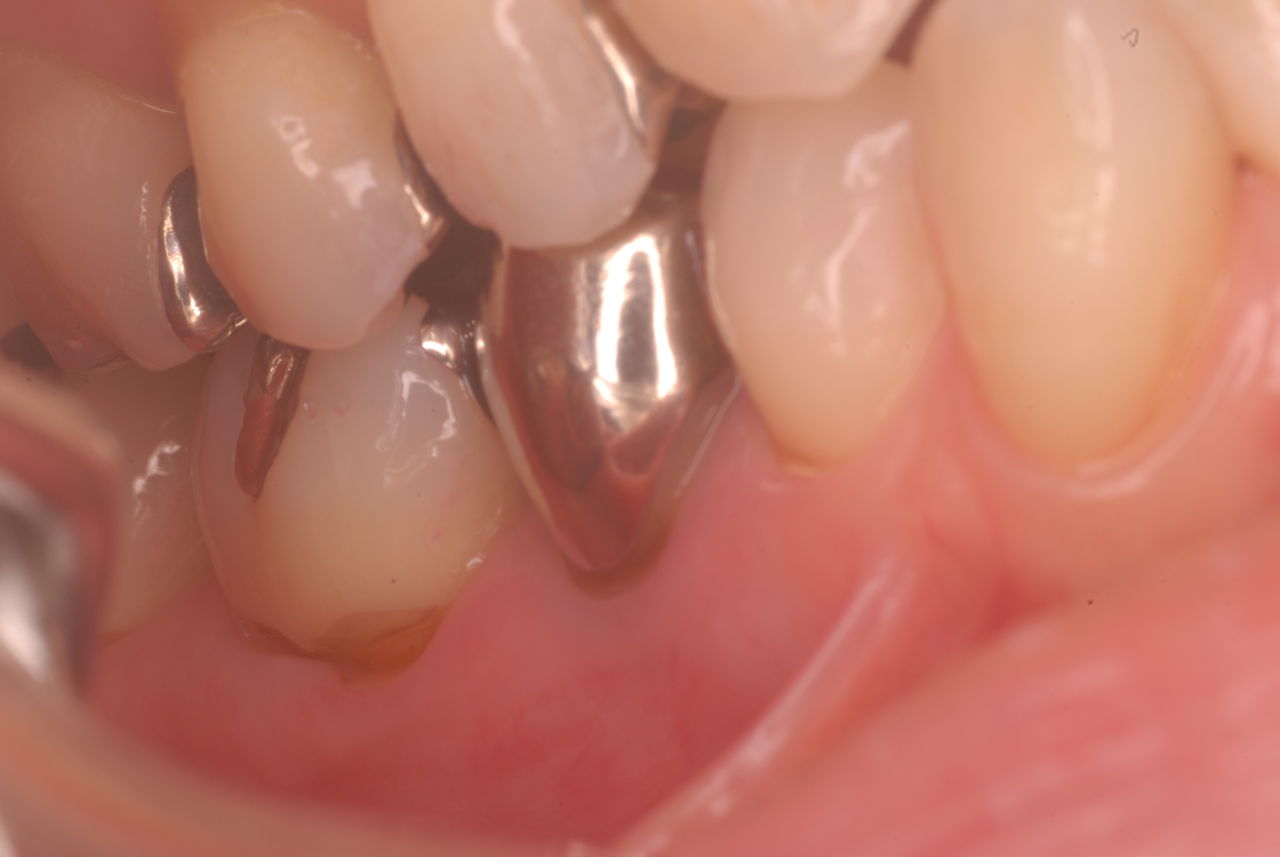

他の都心の矯正歯科で治療中で、ほぼ終了近くの方でした。歯並びで言えば上下の歯が突出していて唇が閉じにくいというのをなんとかしたい。そして歯を抜かないで出来るところを探して都心の矯正歯科への通院となりました。ところが本人曰くよく噛めないというのです。

相談しても“問題無い”の説明だけだそうです。調べたところ歯周病は進行しているし、奥歯の大きい歯2本ずつ計4本はしっかり噛んでいないのです。よく噛めないというのはそのことのようでした。これを矯正的に元に戻すことはできない訳ではありませんが、時間と手間がかかるのは間違いないことです。

歯を削らないといいましても結局歯の間を削りスペースを確保したそうですから、何らかの歯に対する傷害はしているのです。それは虫歯や歯周病を起こしやすい理由にもなりますからこれからも要注意なのです。二年間という貴重な時間を費やしていますから患者本人は大変だったと思います。そして二年間を要したならば更に二年間動かないようにするための入れ歯やマウスピースを装着し続けなければいけないのです。